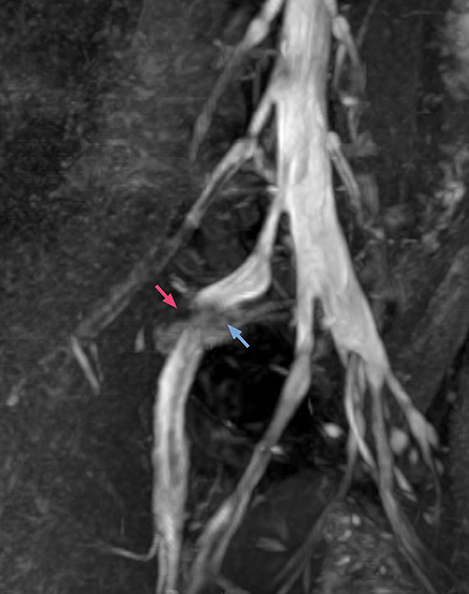

“In such case, we would then browse through axial T2-weighted MR images slice by slice and mentally reconstruct the actual situation based on both radiculography and MRI. Fortunately, NerveVIEW can now very well show nerve courses and presence of nerve compression or edema in one single image series.” “We have often seen NerveVIEW directly depict details of the nerve compression that were not observed by radiculography. Therefore, we think that with NerveVIEW we can reduce the number of invasive examinations, especially for some patients with lumbar plexus symptoms.”

“Before NerveVIEW, diagnosis by MRI alone was sometimes difficult, unless there was a strong suspicion based on clinical symptoms,” says Shoji Yabuki, MD, DMSc, Orthopedic surgeon at Fukushima Medical University School of Medicine. “This is why we routinely perform selective lumbosacral radiculography (nerve root block) and x-ray in such cases. However, radiculography can only depict nerves as far as the contrast agent reaches. When a nerve is distorted by compression, the contrast agent will not pass through this compressed area, preventing us from evaluating the full nerve compression.”

The key concept in MR neurography, Dr. Yabuki stresses, is the ability to directly visualize spinal nerves, versus inferring the presence of pathology indirectly. “Before NerveVIEW, we estimated compression of the nerve by looking for the presence or absence of fat signal on other MR images,” he says.

“For example, in sagittal images, when the presence of fat is observed in the intervertebral foramen, it suggests that there is a margin around the nerve. Similarly, the absence of fat indicates that the nerve is being compressed. So, we used to deduce nerve compression indirectly. With NerveVIEW, however, we can observe the condition of the nerves directly, regardless of the presence or absence of fat. We always prefer such direct observation of anatomy over having to make an inference about it.”

“Although symptoms of typical disc herniation and atypical hernia are very similar, the actual site of herniation is different. It is therefore important to characterize the nerve’s condition both inside and outside of the intervertebral foramina. “Conversely, if we see no abnormality in NerveVIEW, we can assume at least that there is no severe condition that requires surgery. Like this, it can help us avoid unnecessary surgery. NerveVIEW can have a tremendous impact in this way.”

“NerveVIEW is really useful for those cases where a nerve disorder is strongly suspected based on the clinical examination but our regular MRI images do not show any findings. These atypical herniations and spinal canal stenosis, occurring in 5% to 15% of the total lumbar herniation/stenosis cases are our main target when using NerveVIEW,” says Dr. Yabuki.